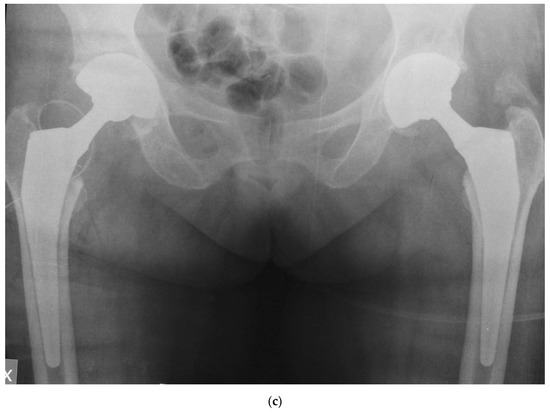

Figure 2 shows the case of a 54 years old male who was admitted to our hospital due to a displaced fracture of his left femoral neck and was in treatment since several years for depression, treated with the G7 modular cementless DM cup with 2 screws and a Taperloc stem on the femoral side.

Figure 2. Displaced fracture of left femoral neck in a 54 years old male (a); dual mobility (DM) modular cup with screw and cementless stem (b).